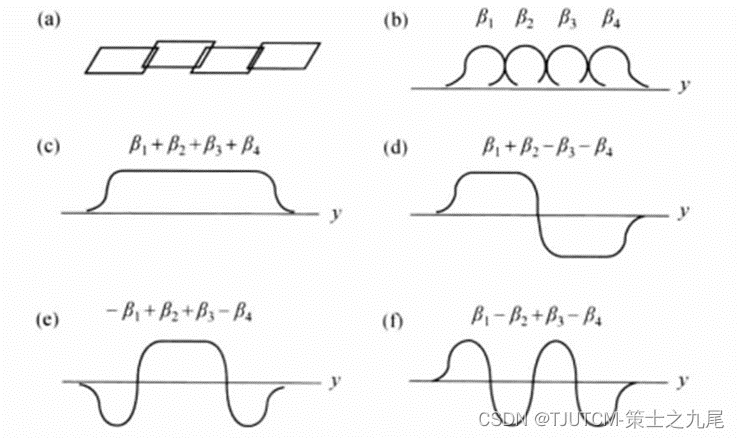

(a)图为可用于SMASH的四线圈阵列

(b)图为线圈灵敏度

©图为线圈灵敏度之和(1)

(d)、(e)、(f)为灵敏度组合

对于SMASH最佳线圈几何或许是沿一直线放置的线圈阵列,虽然对于任意线圈几何SMASH也能产生高质量图像。并行成像也可应用到3D扫描的第二个相位编码。在高场SNR很高,并行成像最有用,最成功的应用之一是对比剂增强的MRA。降低扫描时间对于捕捉团注通过的峰值,缩短屏住呼吸时间是有利的。用SSFP梯度回波序列(比如True FISP)对心脏扫描给出足够的SNR允许加速因子R>=2。这导致较短的屏住呼吸时间、较好的空间分辨或时间分辨。

大多数线圈阵列都专门设计得灵敏度之和近似是一常数,为的是能 给出近似均匀的图像信号(对于均匀物体)。